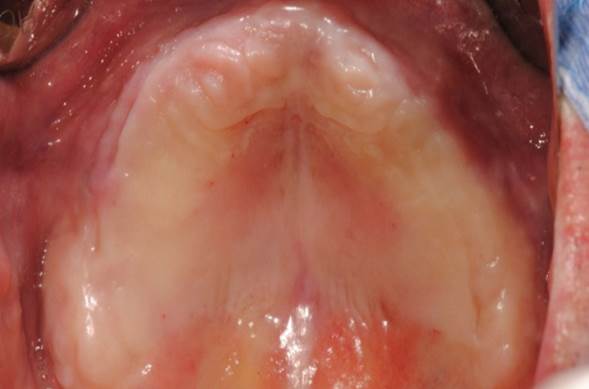

Clinical case: Extraction of all teeth in upper maxilla,

immediate implant placement, & provisionalization

- Courtesy of Dr. Iulian Filipov, Romania -

Keywords

AnyRidge, immediate placement, immediate provisionalization, maxillary fully edentulous case, initial stability, edentulous, Dr. Iulian Filipov, R2GATE, MEGA ISQ

Products:

AnyRidge implant system, Mega ISQ, R2GATE